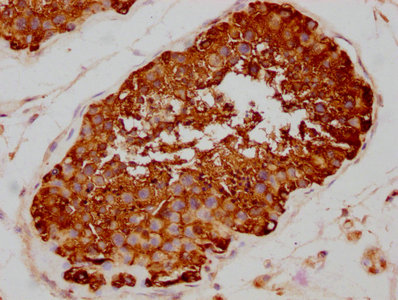

DescriptionHSP90AA1 Recombinant Monoclonal Antibody [4B5]. Unconjugated. Raised in: HEK293F Cell.

ApplicationELISA, WB, IHC, IF, IP; Recommended dilution: WB:1:500-1:5000, IHC:1:50-1:200, IF:1:20-1:200, IP:1:200-1:1000